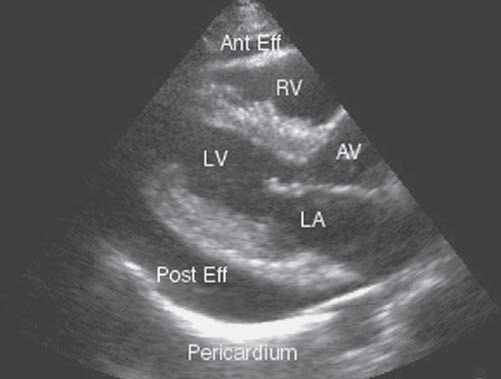

2) 심초음파

: 심낭 삼출의 확인 및 양, 위치평가, 심낭압전 여부 확인을 위해 필수적인 검사이다.

| 정상 | 소량 | 중등도 | 대량 | |

| 용량 | 20~30 ml | < 100 ml | 100~500 ml | > 500 ml |

| M-mode | < 5 mm | 5~20 mm | > 20 mm | |

| 2D 심초음파 | < 1 cm 심장 일부에만 | < 1cm 심장 전체 | > 1cm 심장 전체 | |

| 관찰 심주기 | 수축기에만 관찰 | 심주기 전체에 관찰 | 심주기 전체에 관찰 | 심주기 전체에 관찰 |

1) 심초음파 : 심낭 삼출액과 동반된 우심방 및 우심실의 이완기말 위축, 흡기 시 심실중격의 움직임, swinging heart, IVC plethora 등의 소견을 종합하여 심낭압전 여부를 감별한다.